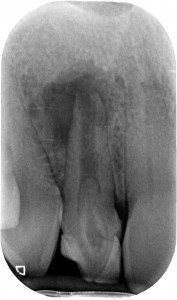

Il fenomeno rappresentato è chiaramente un Dens Invaginatus, meglio conosciuto come Dens in Dente. In realtà esiste una terza definizione, che è quella della mia assistente Roberta che è portatrice sana di un Dancing Dente ???, che è quello che ha capito lei quando ho emesso la diagnosi guardando la rx del suo incisivo laterale di sinistra! Diagnosi che il suo vecchio dentista non aveva saputo fare…

Con tutta probabilità l’affondamento del dente da latte sulla gemma in formazione del 2.2 ha generato una deformazione dell’organo dello smalto che si è appunto invaginato all’interno della papilla dentale, formando un dens in dente, come dimostra la linea radiopaca che si intravede all’interno del dente, che non è nient’altro che smalto. Uno smalto un po’ meno mineralizzato di quello esterno, se guardiamo alla letteratura, ma pur sempre smalto.

Il primo era questo

La proprietaria del dente, una ragazzina di 16 anni, da tempo lamentava gonfiore e dolore che scompariva solo con terapie antibiotiche. Il dentista precedente aveva semplicemente corretto la forma del dente con un composito orrendo. La diagnosi non aveva saputo farla. Aveva solo saputo dire che era un dente che si poteva solo estrarre.

Con l’ausilio della Cone Beam sono riuscito a identificare che il dente aveva due canali e una radice molto palatoversa: per accedere a questi canali, separati tra loro dall’istmo di smalto invaginato, potevo fare una cavità perpendicolare al dente a livello vestibolare e una palatina.